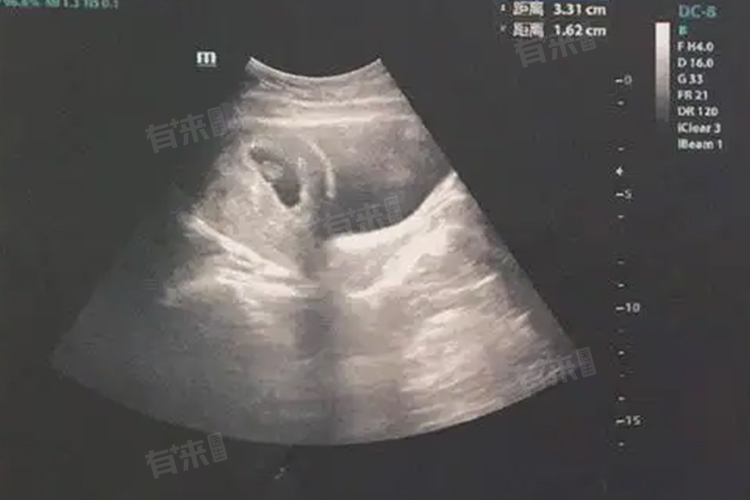

1、超声波检查:通过B超检查子宫内膜恢复情况,确认宫腔内无残留组织,排除子宫穿孔或感染等并发症。